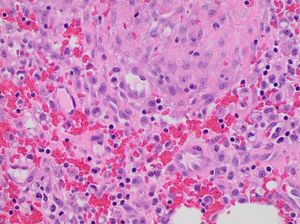

육아 조직은 상처 치료 과정에서 나타나는 조직으로, 밝은 적색 또는 분홍색을 띠며 부드럽고 촉촉한 특징을 보인다. 육아 조직은 세포외 기질, 면역, 혈관 신생으로 구성되며, 섬유아세포가 세포외 기질을 생성하고, 대식세포와 호중구가 면역 반응을 담당하며, 혈관 신생을 통해 영양 공급 및 노폐물 제거를 돕는다. 과도한 육아 조직은 "자부심 살"이라고 불리기도 한다.

육아 조직은 상처 치료 단계에 따라 다른 모습을 보인다.

육아 조직은 다양한 세포 유형을 지원하는 조직 기질로 구성되며,[3] 대부분 다음 기능 중 하나와 관련될 수 있다.